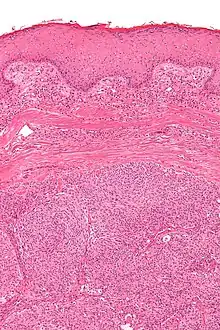

Micrograph showing an acrospiroma. H&E stain. | |

Hidradenoma refers to a benign adnexal tumor of the apical sweat gland.[1][2] These are 1–3 cm translucent blue cystic nodules. It usually presents as a single, small skin-colored lesion, and may be considered closely related to or a variant of poromas.[3] Hidradenomas are often sub-classified based on subtle histologic differences, for example:[4]

Discussion of sweat gland tumors can be difficult and confusing due to the complex classification and redundant terminology used to describe the same tumors. For example, acrospiroma and hidradenoma are synonymous, and sometimes the term acrospiroma is used to generally describe benign sweat gland tumors. In addition, a single lesion may contain a mixture of cell-types.[2] There has also been a change in understanding about how tumors that were previously believed to strictly derive from specific sweat gland types may, in fact, derive from both eccrine or apocrine glands.[5][6]